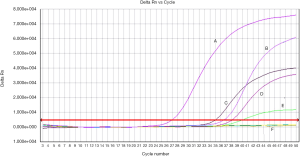

Methylation frequency of RASSF1A and APC

Methylation status of RASSF1A and APC for 89 patients as well as 23 normal samples was examined using QMSP. Representative results of methylation analysis by QMSP were shown in Figure 2, and detailed data regarding the frequency of aberrant methylation were summarized in Table 2.

For RASSF1A, the methylation rate of three different sample types (plasma, serum and tissue) all showed significant differences among three groups. Significant differences for APC were observed in plasma and tissues. However, the benign disease group showed a relatively lower methylation frequency. No methylation for both of the two genes was found in the healthy group. The difference between benign disease group and healthy group was not significant. Besides, the smoking rates of caner group and benign group were both around 60%.